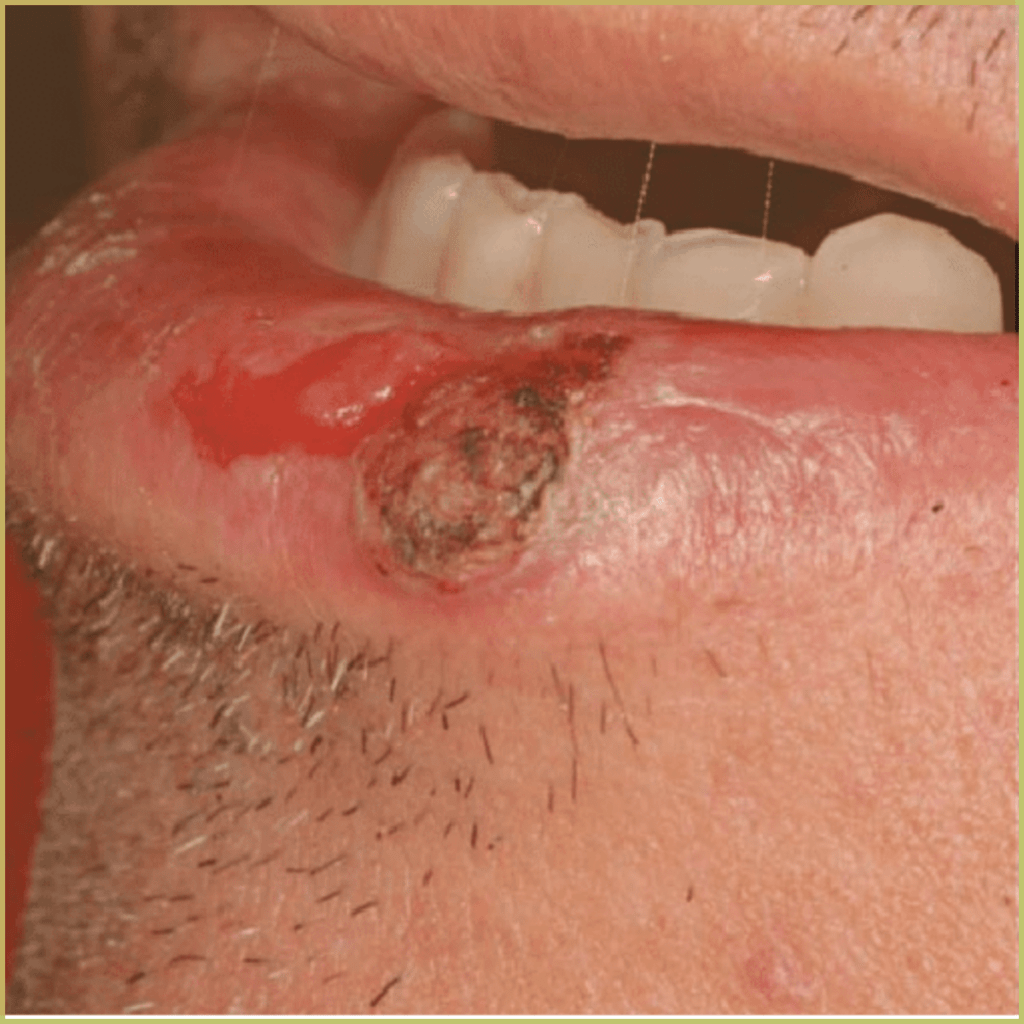

SQUAMOUS CELL CARCINOMA

Squamous Cell Carcinoma (epidermoid carcinoma) is the most common head and neck malignancy. The tongue is the most common subsite and is associated with higher mortality when compared to other affected areas. Risk factors include tobacco-derived carcinogens, excessive alcohol consumption, and possibly exposure to human papillomavirus (HPV 16 and 18). The common clinical presentation includes:

- Early lesion – white or red-white macule (leukoplakia, erythroplakia).

- Mature lesion – ulceration, induration, elevated margins.

- Advanced lesion – may impede function/movement or erode adjacent bone.

- Most likely found on the lateral surface of the tongue, floor of the mouth, and lower lip vermilion.

- Trismus or cervical lymphadenopathy may indicate metastases.

Diagnosis is based on the lesion history, clinical presentation and microscopic findings, which may include:

- Invasive islands and cords of epithelial cells.

- Nuclear pleomorphism with large nuclei (increased nuclear to-cytoplasmic ratio).

- Dyskeratosis.

- Architectural disorganization of proliferating cells.

Your differential diagnosis should include:

- Chronic traumatic ulcer.

- Primary syphilis.

- Actinic keratosis.

- Keratoacanthoma.

- Wart.

- Another neoplasm (basal cell carcinoma or melanoma).

Treatment options include:

- Surgical excision.

- Combined surgery and radiation therapy.

- Chemotherapy.